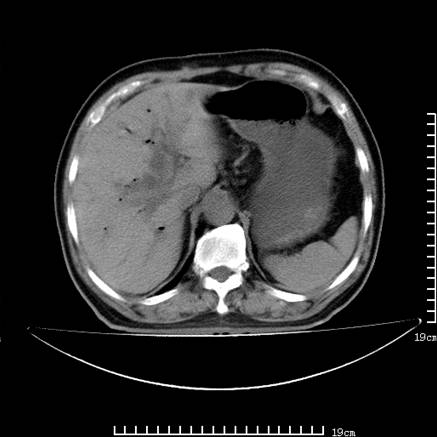

以下是引用zsl6918在2008-7-19 21:53:00的发言:[br]胆总管结石并胆系感染,胆囊切除术后改变。

以下是引用sch2008在2008-7-19 22:03:00的发言:[br]肝内胆管及胆总管积气,并胆总管结石,考虑;胆囊切除术后,胆系感染

以下是引用xinliheng001在2008-7-19 21:59:00的发言:[br]胰头段胆管结石肝内外胆管扩张积气。